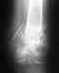

травма была получена 3 апреля (на сборах)

ренген был сделан 30 мая

МРТ 03 июля

боль присутствует до сих пор, подвижность ноги сильно ограниченна.